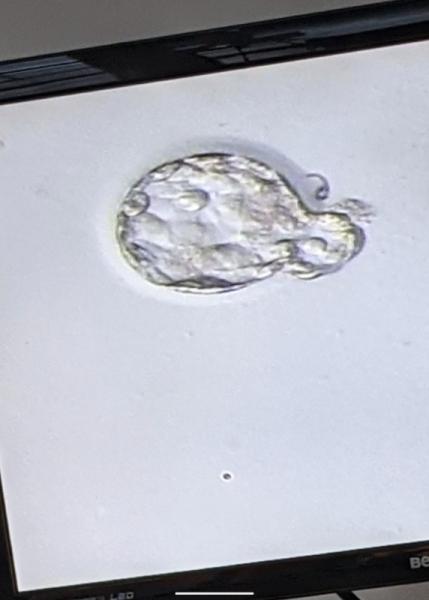

Und noch ein Bild von der Eisbärchen Blasto

Ja ich finde sie sehr gut,auf den einen bild schlüpft sie sogar